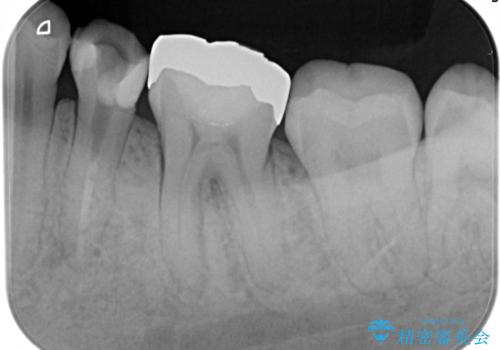

精密根管治療。大臼歯イニシャルケース

- 奥歯がズキズキ痛いことを主訴に来院されました。

検査の結果、診断を症候性不可逆性歯髄炎、症候性根尖性歯周炎とし抜髄を行っております。

根管充填はCWCTにて行なっております。

根管形成はマルテンサイト相を有するNi-Tiロータリーファイル(NEX MS)使用。